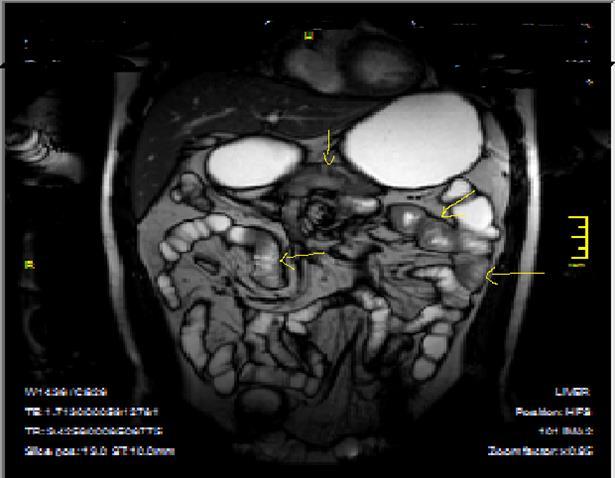

Figure 4a.Mucosal involvement and lack of opacified ileal segments with loss of intestinal folds and increased bowel wall thickness due to Crohn’s disease on T2W coronal sequence after OCA, presented at 37 years old male with moderate Crohn’s disease.

Figure 4b.Mucosal, luminal and bowel wall involvement in Crohn’s disease with skipped lesions, seen at T2W axial image after OCA, presented at 45 years old male with severe inflammatory disease.